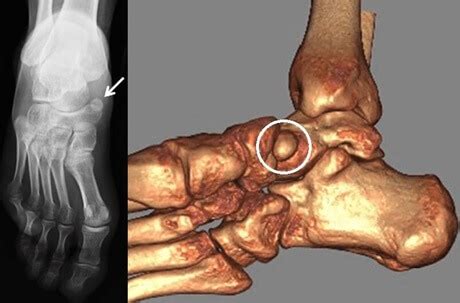

accessory navicular bone pain  symptoms treatment

accessory navicular bone pain  symptoms treatment 460×303 accessory navicular bone pain symptoms treatment from www.foot-pain-explored.com

accessory navicular bone understanding  anatomy  implications 1640×924 accessory navicular bone understanding anatomy implications from www.spinalogy.com

accessory navicular bone xray  susan cummings blog 1500×1600 accessory navicular bone xray susan cummings blog from storage.googleapis.com